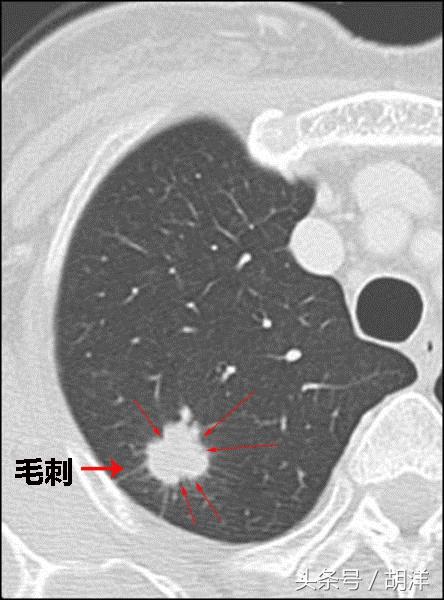

肺部有小太阳一样的结节影

肺癌一般来说呈渗透性生长,总有一些癌细胞会很快的长到正常细胞之间,并向前延伸,就像老巢周围有无数的触须,又像周围有很多霞光的太阳,另外肿瘤会分泌一些物质让周围血管自动长入肿块,也会形成这个表现,这种表现一般来说是肺癌的表现,需要特别当心。